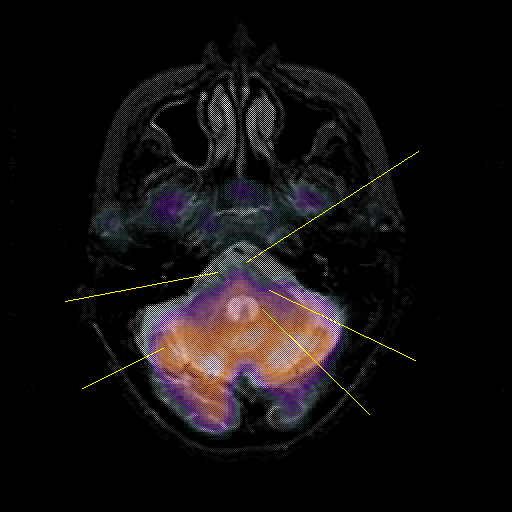

overlay : Slice 13

Slice 13

MRCBFCBF with

Unlabeled

Pointers

Labeled